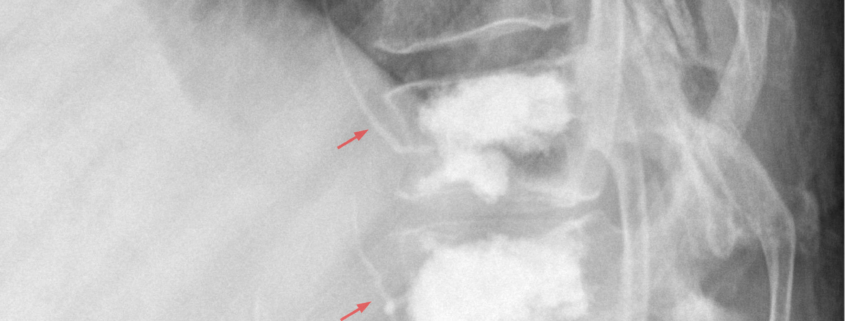

When these measures are not enough, your doctor may recommend a procedure like Kyphoplasty, where a balloon is used to create a space into which a type of bone cement called polymethylmethacrylate is injected to stabilize the fracture.

• Imaging Tests: X rays, CT scans, or MRI may be used to visualize the condition of the vertebrae and confirm the nature of the fracture.